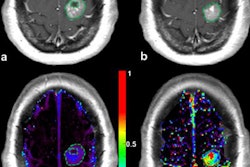

A total of 17 patients (10 men, seven women, mean age 38) were examined using a Philips Ingenuity TF PET/MR system. The device consists of two separate machines linked through a single patient table, allowing sequential imaging. Standard imaging protocols of both modalities were combined.

In all cases, diagnostic quality images were obtained for both modalities in a single session. A total of 13 subjects had positive findings, which were confirmed by clinical follow-up in seven cases. One false positive PET uptake was due to radionecrosis. The remaining five positive subjects showed metabolic changes, the interpretation of which is currently under evaluation with clinical follow-up (e.g., global cortical hypometabolism and basal ganglia hypermetabolism in a case of obsessive compulsive disorder). Of the four negative studies, no false negatives were identified with clinical follow-up.